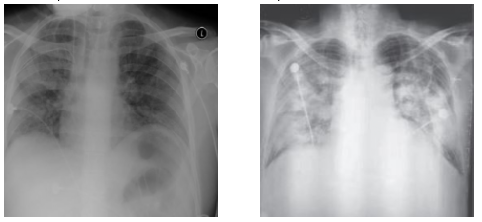

Get Chest Networks Images. I'm having problems with the structure of the networking chest. However, this project will provide an overview of how to build a model from scratch to detect pneumonia using tensorflow and…

Figure 2 from Computer-Aided Tuberculosis Detection from ...